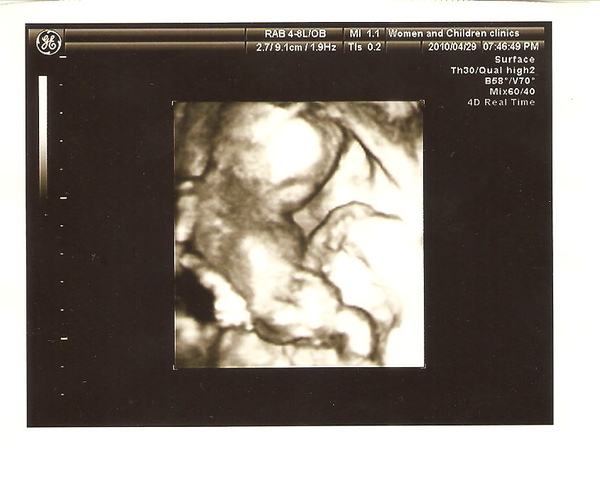

小孩子很OK,超音波東轉西照地,突然間!!!我們看到了那個...╭^╮,從屁股看過去的角度

超明顯的,醫生還沒說我們兩個互看一眼:啊!男生!?

醫生也馬上說:是男生喔~沒人告訴過你們喔?超明顯的,不會翻盤了,就是男生!

15W生殖器已經發展完成,翻盤機會不大了,而且我看很少出錯的!